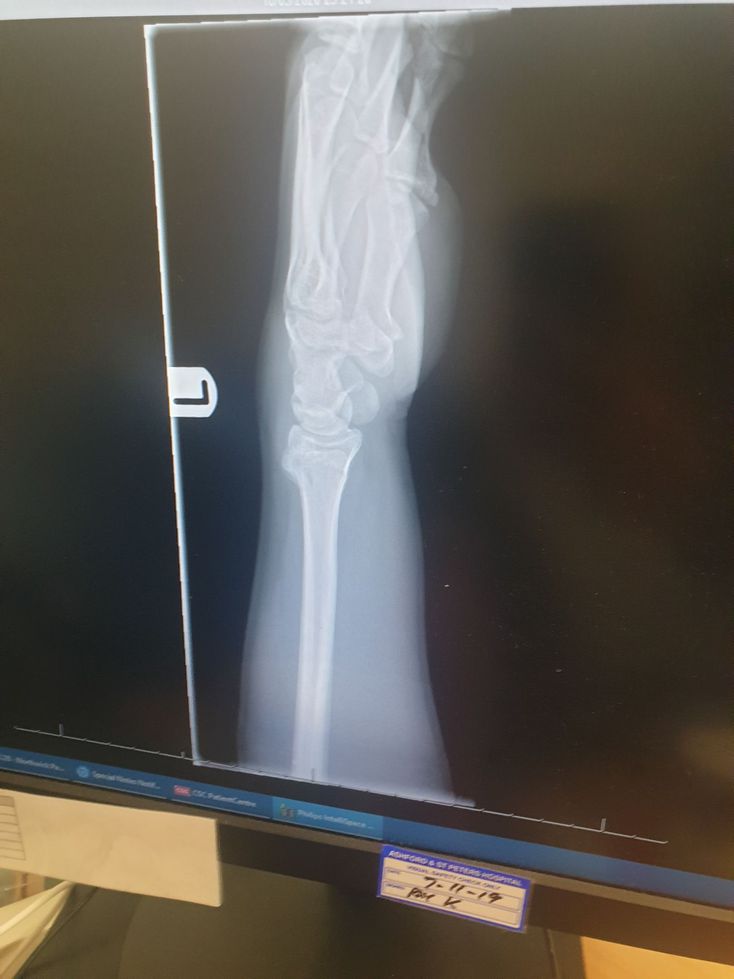

Distal radius fracture

How bad is this and how would you treat it?